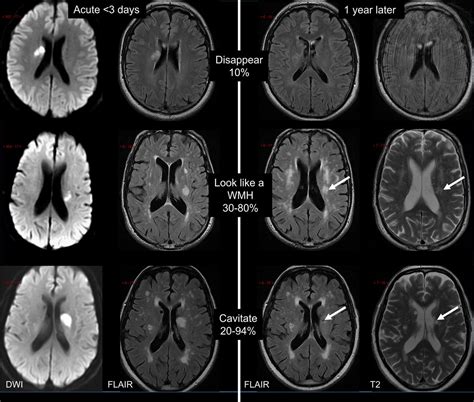

The primary method for diagnosing Small Vessel Disease is through neuroimaging, specifically Magnetic Resonance Imaging (MRI). An MRI is highly sensitive to the changes associated with this condition. Radiologists look for specific markers on the brain scans, such as:

• White Matter Hyperintensities (WMH): Bright spots on the MRI that indicate areas of damaged white matter.

• Lacunar Infarcts: Small, fluid-filled cavities resulting from previous microscopic blockages.